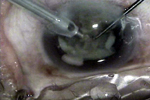

部分视频画面

手术者-温州医学院眼视光医院 赵云娥主任

过熟期过熟期硬核白内障软壳技术